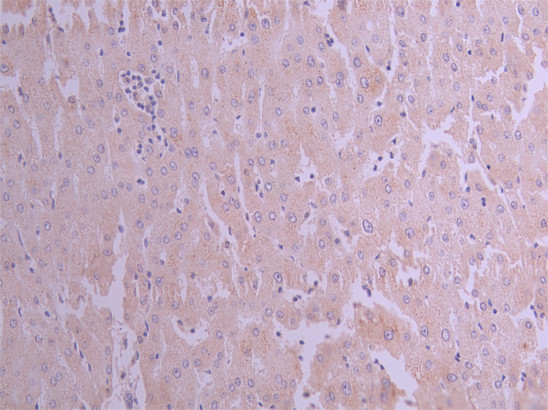

IHC image of CSB-RA002005MA1HU diluted at 1:50 and staining in paraffin-embedded human liver tissue performed on a Leica BondTM system. After dewaxing and hydration, antigen retrieval was mediated by high pressure in a citrate buffer (pH 6.0). Section was blocked with 10% normal goat serum 30min at RT. Then primary antibody (1% BSA) was incubated at 4°C overnight. The primary is detected by a Anti-Human lgG, Fcy Fragment Specific labeled by HRP and visualized using 0.05% DAB.

IHC image of CSB-RA002005MA1HU diluted at 1:50 and staining in paraffin-embedded human liver cancer performed on a Leica BondTM system. After dewaxing and hydration, antigen retrieval was mediated by high pressure in a citrate buffer (pH 6.0). Section was blocked with 10% normal goat serum 30min at RT. Then primary antibody (1% BSA) was incubated at 4°C overnight. The primary is detected by a Anti-Human lgG, Fcy Fragment Specific labeled by HRP and visualized using 0.05% DAB.

IHC image of CSB-RA002005MA1HU diluted at 1:50 and staining in paraffin-embedded human testis tissue performed on a Leica BondTM system. After dewaxing and hydration, antigen retrieval was mediated by high pressure in a citrate buffer (pH 6.0). Section was blocked with 10% normal goat serum 30min at RT. Then primary antibody (1% BSA) was incubated at 4°C overnight. The primary is detected by a Anti-Human lgG, Fcy Fragment Specific labeled by HRP and visualized using 0.05% DAB.